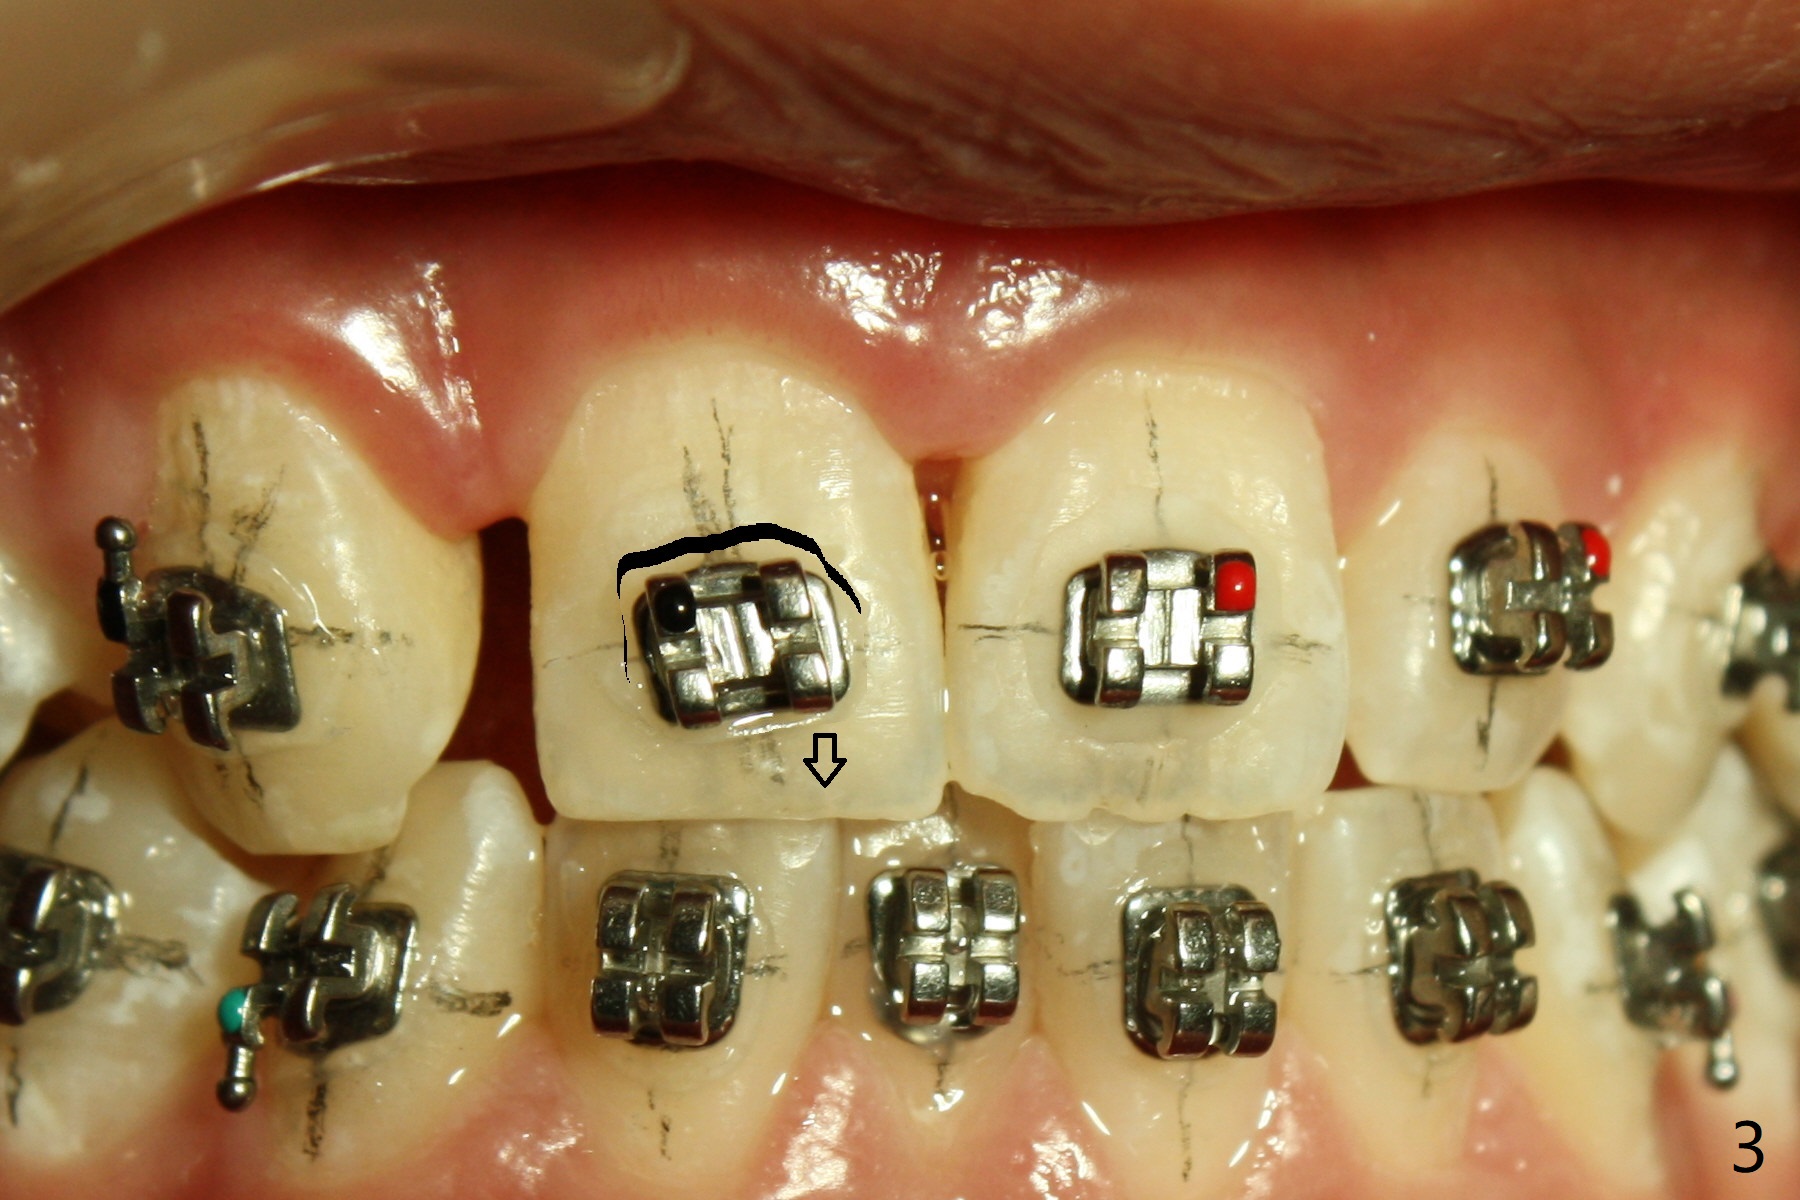

A 15-year-old man finishes orthodontic treatment for congenital missing lateral in 13 months. Molar Class I relationship remains the same (Fig.1,2,4,5). The upper diastemata mesial to 4s (Fig.4,7") close with correction of the upper midline deviation (Fig.2'-4'). The kid is unpleased with the elongated UR1 (Fig.2',3'). In fact it is a preexisting condition (Fig.2 arrow, 2"), but bracket placement at UR1 should have been overcorrected (incisal placement, Fig.3"). The intrusion should be done (Fig.4") before closure of the diastemata, since anchorage may be weakened when the separation between UR1 and 3 increases by using open coil spring. To prevent immediate relapse of the diastema between the upper central incisors, a fixed retainer is placed lingual before debracketing (Fig.6,6',6").